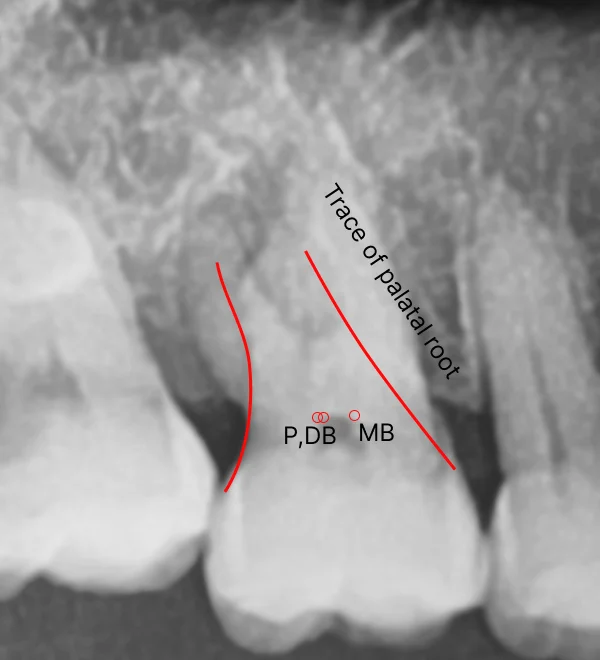

🎯 Finding the Hidden Palatal Root

Palatal roots are often tricky to locate, but now that we have a real 3D model as a reference, spotting its shape and positioning becomes much easier.

Tracing hidden palatal root

Now, let’s train our eyes to detect these subtle shadows in future cases. By practicing with actual 3D models overlaid onto X-rays, we can improve our ability to mentally reconstruct the tooth’s spatial anatomy.